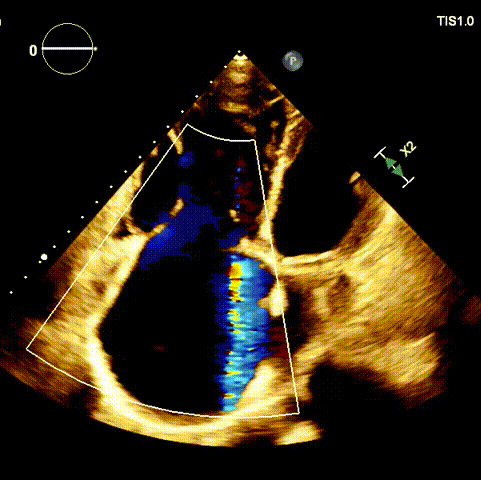

術前超聲

1.二尖瓣位機械瓣位置及功能未見異常;2.雙房及右室明顯擴大(左房收縮容積115ml,右房收縮容積370ml,右室中段左右徑65mm,右室FAC37%),下腔靜脈及冠狀靜脈竇擴張(下腔靜脈直徑44mm,冠狀靜脈竇直徑22mm);3.極重度三尖瓣反流(FTR 6+)。